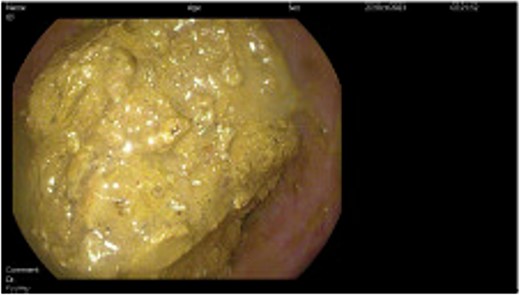

Subsequently, the patient underwent a series of three sigmoidoscopies on Day 2, 3, and 5 of her hospital stay (Fig. 2) after receiving polyethylene glycol prior to each intervention. During the first procedure, attempts at disimpaction of the fecaloma were made. Techniques used included saline lavage along with manual disimpaction with forceps and snares. Despite these efforts, disimpaction of the fecaloma was only minimally successful, leaving a significant amount of retained stool in the descending colon. The procedure was aborted, and the bowel regimen was continued along with the administration of a fleet enema; these measures brought only minimal relief. The following day, another sigmoidoscopy was performed, revealing a 35–40 cm fecaloma almost completely obstructing the bowel lumen with surrounding mild inflammation and ulceration. Attempts were made to dislodge the fecaloma using a net grasper, biopsy and snare, infusion of hydrogen peroxide diluted with saline, and an injection with mineral oil and an endoscopic retrograde cholangiopancreatography balloon. However, this attempt was unsuccessful, and a decision was made to repeat the sigmoidoscopy after giving the patient polyethylene glycol and fleet enemas for 2 days. Following this, the patient was able to pass more flatus and had a small watery bowel movement.

Direct visualization of the fecaloma causing colonic obstruction was obtained during the endoscopic intervention performed during hospital admission.